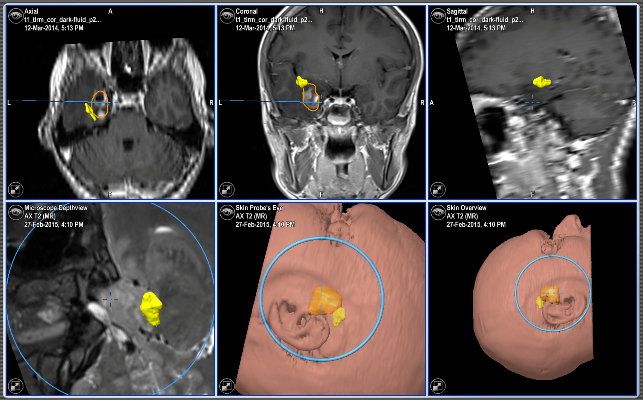

Cazul s-a dovedit a fi unul din categoria celor cu dificultate majoră. Pe lângă dimensiunile mari ale tumorii, a edemului cerebral perilezional, s-a constatat că tumoarea se află în vecinătatea imediată a zonelor verbale care ar putea suferi în timpul operației tradiționale. Pentru a elucida mai bine rapoartele anatomice, pacientul a realizat o investigație RMN cu utilizarea mai multor regimuri speciale: regim neuronavigație, DTI, DWI, Fiber Tracking și Mappingul Cortical preoperator prin Rezonanță Magnetică Funcțională – fMRI. Astfel, echipa chirurgicală a obținut informații foarte utile despre rapoartele anatomice regionale și distribuția diferitor funcții pe scoarța cerebrală. Aceste date au fost necesare pentru integrarea cu sistemul de neuronavigație.

Anterior intervenției, familia pacientului a înaintat anumite condiții, care, de fapt, au reprezentat și una din principalele probleme – păstrarea vorbirii, a mișcărilor și a capacității de gândire după înlăturarea totală a tumorii. Aceste obiective puteau fi satisfăcute numai prin realizarea operației în plină conștiență și cu prezența unui contact verbal deplin cu pacientul în timpul înlăturării tumorii, fapt care a fost realizat.